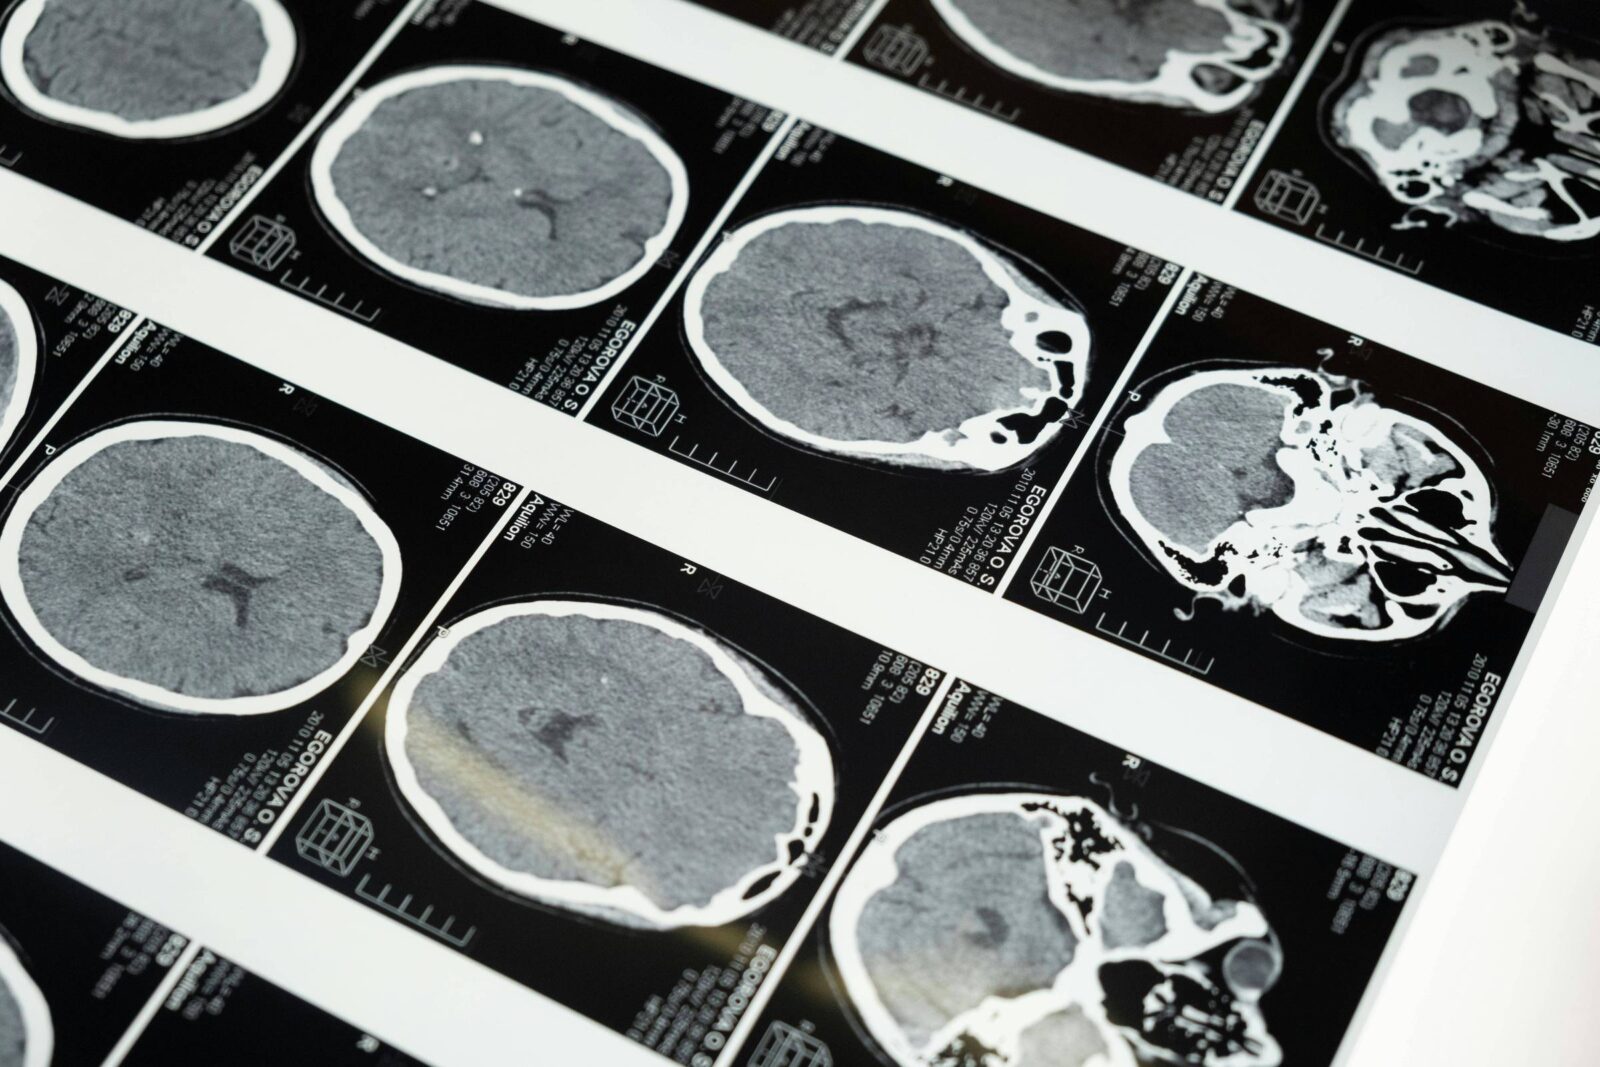

A técnica, considerada não invasiva, consiste em aplicar uma corrente elétrica contínua de baixa intensidade na cabeça para modular a atividade cerebral. Já tem sido aplicada para tratar alguns casos de depressão, bem como testada na recuperação de pessoas com desordens neurológicas, entre elas o AVC (acidente vascular cerebral). No caso do Parkinson, a estimulação elétrica transcraniana também tem sido empregada, mas segue sem um protocolo clínico definido.

A técnica utilizada na pesquisa consiste em modular o funcionamento dos neurônios por meio de um aparelho com dois eletrodos que geram uma corrente elétrica de baixa intensidade (2 miliamperes) que atravessa a região mais superficial do cérebro durante 20 minutos. No caso dos voluntários com Parkinson, ela foi aplicada sobre uma área cerebral conhecida como córtex motor primário —associado à resposta postural e ao controle do movimento.

“Ao gerar uma corrente elétrica de baixa intensidade no cérebro podemos modular a prontidão dos neurônios. Essa estimulação não gera transmissão de impulso nervoso, mas modula o potencial de membrana para facilitar que ela aconteça”, explica.

De acordo com Beretta, a ideia é, a partir dos eletrodos, aumentar a excitabilidade neuronal (e possivelmente a atividade) do córtex motor, que está hipoativo nos pacientes com Parkinson. “Essa modulação permite facilitar a atividade neural para que, quando necessário, o cérebro dispare o que chamamos de potencial de ação [mecanismo básico para a comunicação entre os neurônios e para a contração muscular], fazendo com que aumente o número de disparos neurais nas áreas corticais e subcorticais envolvidas na recuperação da estabilidade e do equilíbrio postural”, diz.